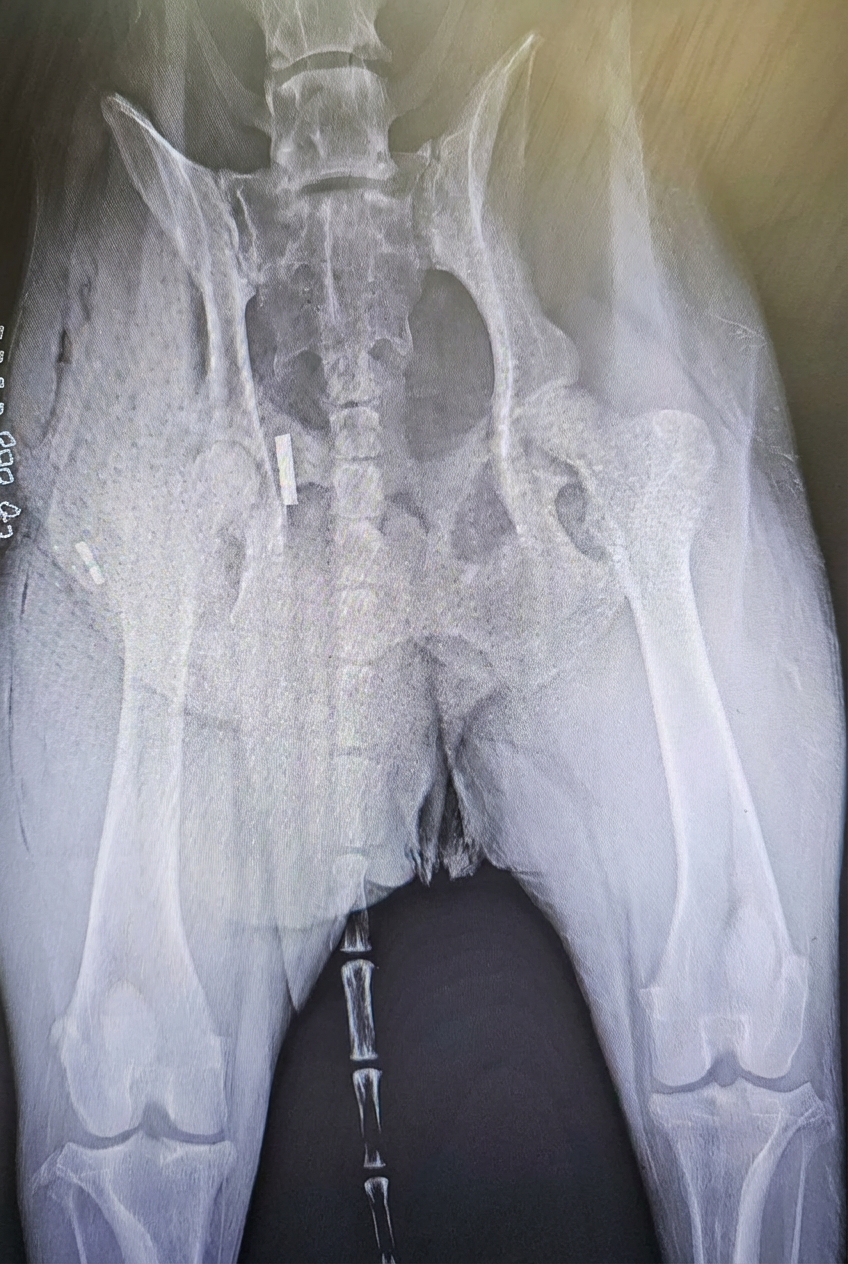

A toggle procedure is a surgical technique used to repair a dislocated hip (most often a craniodorsal hip luxation) in dogs.

Instead of replacing the natural ligament that holds the ball of the hip in the socket, the surgeon places a strong synthetic “toggle” (implant) through small tunnels in the hip socket and the head of the femur. This artificial ligament holds the hip ball securely back in the socket while the surrounding tissues heal and tighten.

The goal is to restore a stable, pain‑free hip so your dog can return to comfortable walking and normal activity after an appropriate healing and rehab period